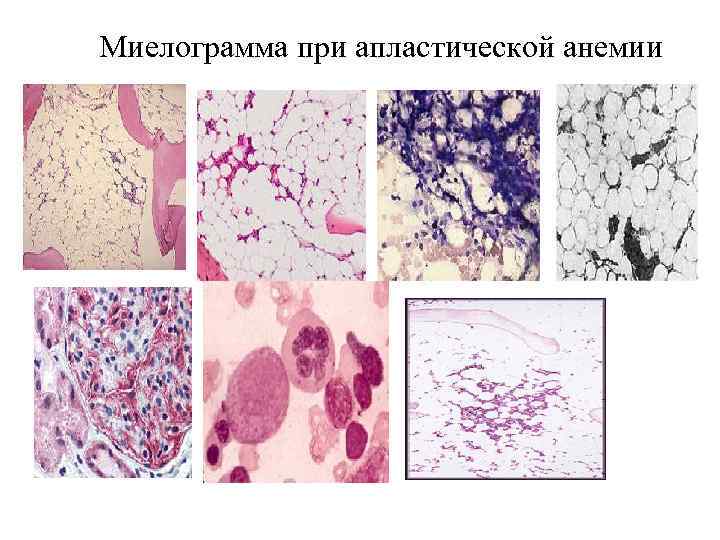

Миелограмма при апластической анемии

Миелограмма при апластической анемии При пункционной биопсии костного мозга (в миелограмме) отмечается малое количество ядросодержащих клеток (миелокариоцитов) или они совсем отсутствуют (трехростковая панцитопения), при гистологическом исследовании отмечаются замещение жиром деятельного костного мозга пунктат костного мозга - трехростковая панцитопения, жировая гиперплазия; культивирование костного мозга и изучение КОЕк; трепанобиопсия — замещение жиром деятельного костного мозга; признаки сосудистого и клеточного гемолиза